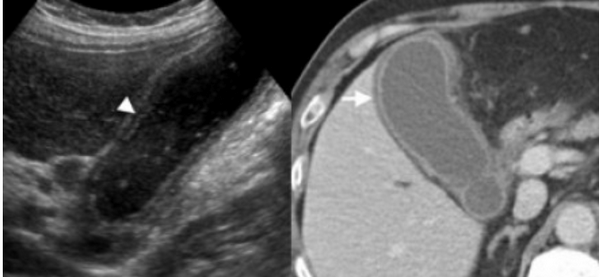

74 — летнему мужчине выполнено УЗИ желчного пузыря. Диагноз: острый некалькулезный холецистит. На левой сонограмме стрелкой указано утолщение стенок желчного пузыря. В просвете желчного пузыря взвесь. На правой сонограмме у того же пациента при исследовании в доплеровском режиме выявлен еще один признак воспаления — гиперемия.

Представлен больной с хроническими болями в правом подреберье, который ежедневно воздерживался от еды с вечера. Утолщение слабо выраженное и не является физиологическим. Также визуализируются обструкция и камень. После УЗИ данному больному был поставлен диагноз — хронический холецистит.